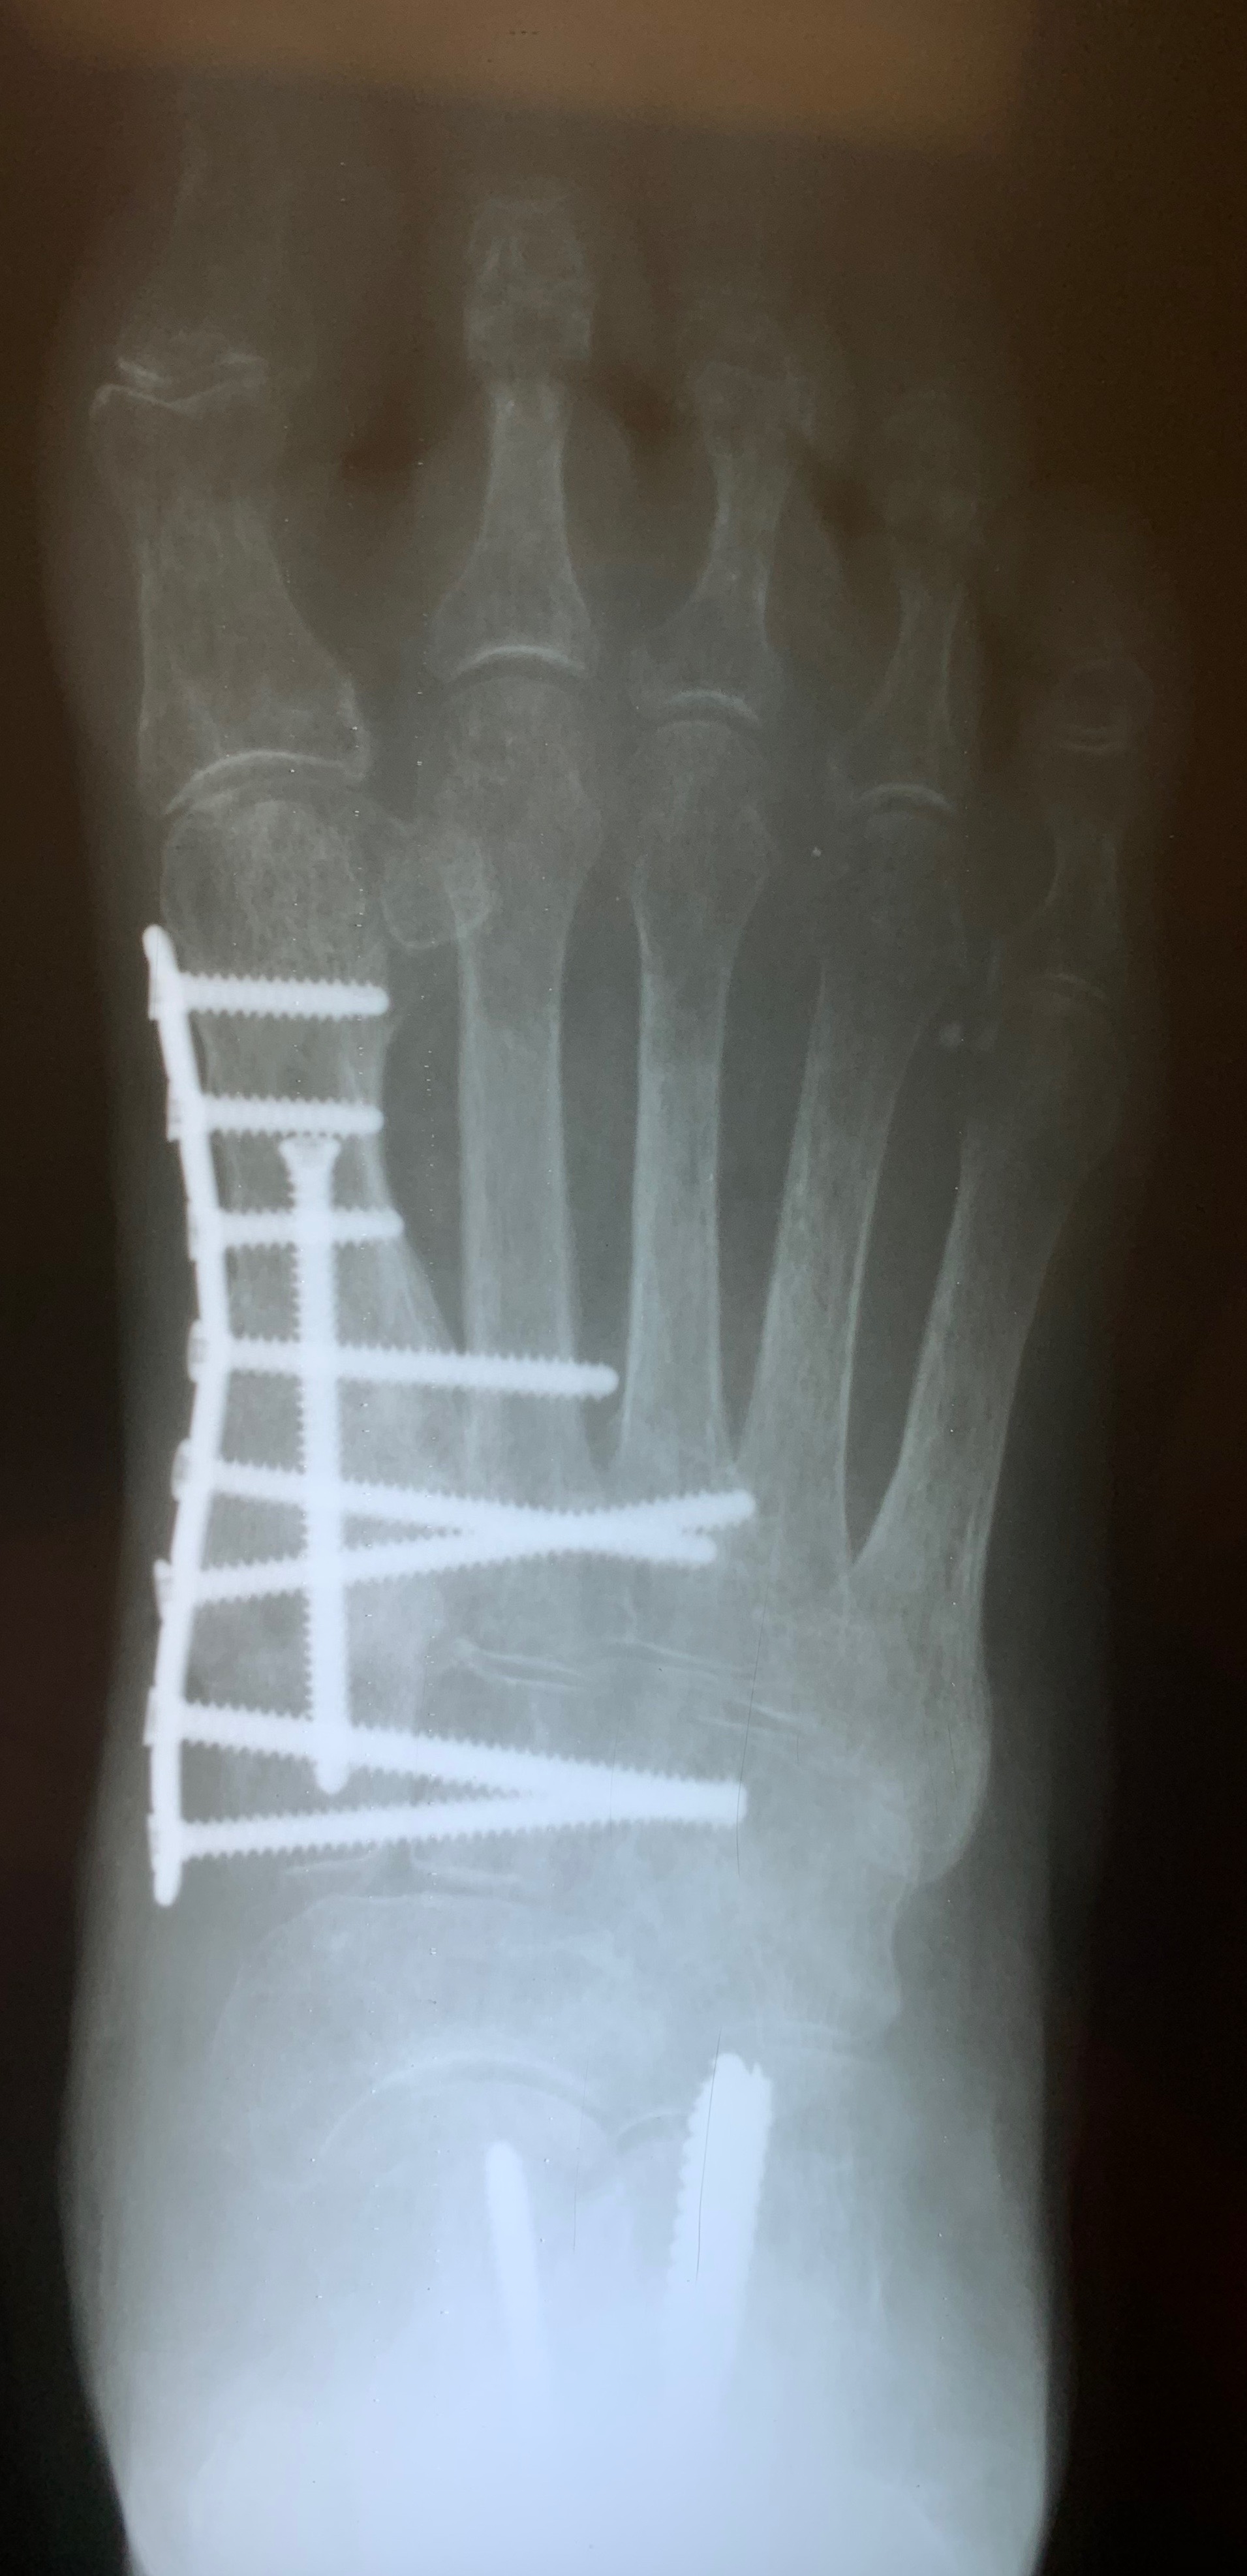

The same principles apply to the foot and ankle. Autogenous bone grafting may be beneficial in many situations including replacing bony defects as well as aiding in deformity correction. Use of autogenous graft allows the foot and ankle surgeon to perform a “positional arthrodesis,” allowing reduction of the deformity with anatomic alignment followed by shear-strain bone grafting across the arthrodesis/fracture site. This enables surgeons to obtain optimal surgical correction while providing the proper environment for stimulation of bony healing. Autogenous grafting for foot and ankle surgery often has limited morbidity as it is within or near the surgical site itself. It is also cost-effective and avoids risks of disease transmission.

We often utilize autogenous grafting for “positional arthrodesis” procedures. A positional arthrodesis allows for optimal positioning and fixation while often leaving a gap or defect due to translating an abnormal or malaligned position to a more anatomic or aligned position. Often the optimal position does not allow for 100 percent bony contact without the risk of shortening or malposition, thus leaving the surgeon with a bony deficit. One may backfill these defects with autogenous bone graft and maintain adequate positioning. However, we recommend as much bony contact as possible while also obtaining optimal position and maximal stability.

Backfilling a fusion or fracture site allows one to limit the amount of shear-strain across the arthrodesis/fracture site. One can define shear-strain as the angular changes between two line segments. Too much shear or strain across a fusion site will result in failure of the fusion, but a construct that is too stiff can lead to failure as it may not allow enough micromotion to stimulate bony healing.23

For those who prefer maximal primary bony contact during fusion, it remains unclear if there are gaps between bony contact on a microscopic level. Backfilling with autogenous graft during positional arthrodesis facilitates bony spot welding across the fusion site. It allows for deformity correction with some bony contact between the fusion/fracture site while providing structural fixation across the fusion site with a biologically friendly environment. Shear-strain bone grafting allows micromotion to occur in a controlled fashion, thus maintaining position but allowing for increased vascularity and bony healing.24 Perren and colleagues found that primary and secondary bone healing occur at the same rate.24 This concept allows utilization of autogenous grafting not only for reconstructive procedures but also in the setting of trauma.